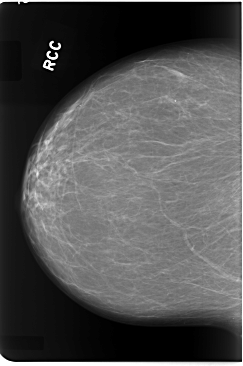

C_0082_1.RIGHT_CC

RIGHT_CC LINES 5856 PIXELS_PER_LINE 3888 BITS_PER_PIXEL 12 RESOLUTION 50 NON_OVERLAY